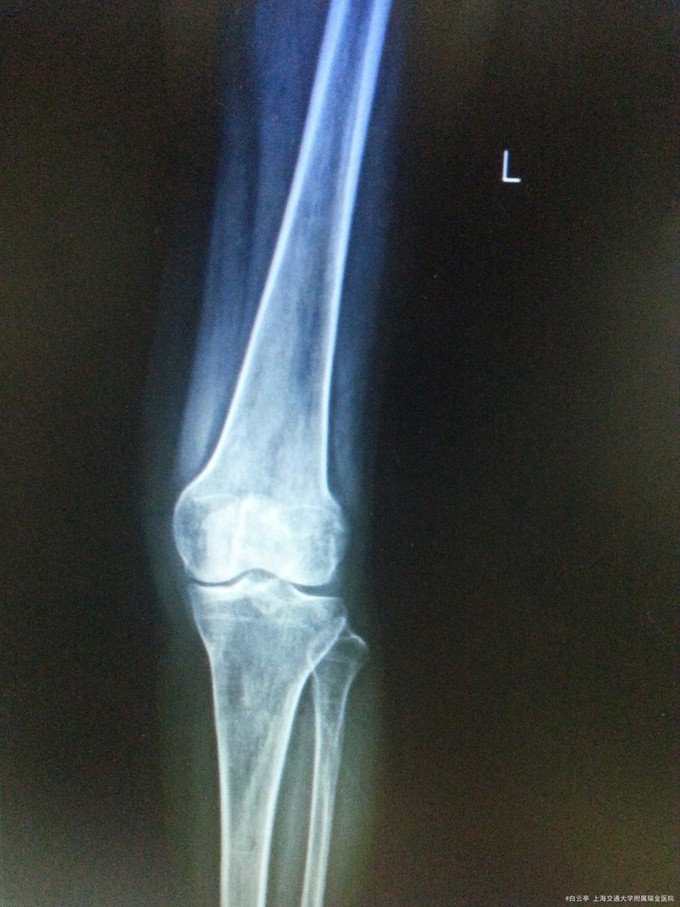

诊断:左髌骨骨折术后取出内固定装置 治疗:入院评估患者骨折恢复可,行“左髌骨骨折术后取出内固定装置”

随访:术后2周患者膝关节手术切口愈合好。活动度及肌力良好 讨论:髌骨张力带术后患者,通常9个月至1年后拔除内固定装置。请讨论各位同道会选择经过多长时间